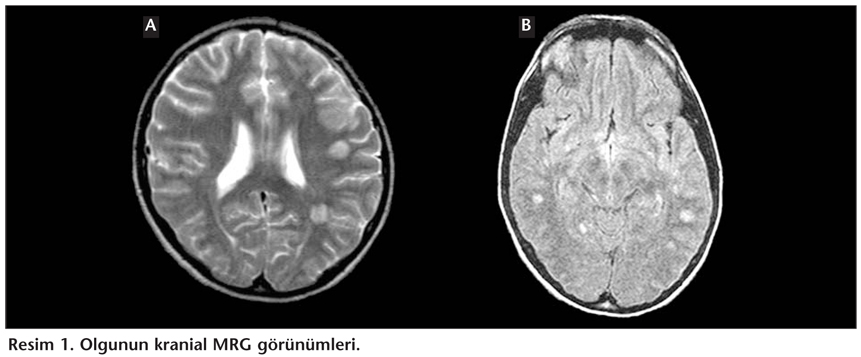

Onbeş yaşında erkek hasta, bir hafta önce ateş, baş ağrısı, bulantı ve kusma şikayetleriyle özel bir sağlık merkezine başvurmuş. Üst solunum yolu infeksiyonu (ÜSYİ) tanısı konularak amoksisilin-klavulanik asit ve parasetamol tablet verilmiş. İlaçları iki-üç gün düzenli kullanmasına rağmen şikayetlerinin geçmemesi ve baş ağrısının artması üzerine hastanemiz acil polikliniğine başvurdu. Ateş, baş ağrısı ve ense sertliği saptanması üzerine akut menenjit ön tanısı ile yatırıldı. Hastanın şuuru açık, koopere ve oryante idi. Oral ateşi 40°C, nabız sayısı 60/dakika, solunum hızı 20/dakika, kan basıncı 100/70 mmHg idi. Fizik muayenesinde bu bulgulara ilaveten ense sertliği (++) saptandı. Hastaya göz dibi muayenesi sonrası lomber ponksiyon yapıldı. Gelişindeki laboratuvar bulguları: Lökosit sayısı 17.500/mm3 (nötrofil: 14.000/mm3), hemoglobin 12.6 g/dL, hematokrit %37.6, trombosit sayısı 382.000/mm3 olup, tam idrar tetkikinde özellik yoktu. Akciğer grafisi normaldi. Beyin omurilik sıvısı (BOS) bulguları: Basınç artmış, görünüm berrak, 180 hücre/mm3 (%60 lenfosit), glikoz 59 mg/dL (kan glikozu: 109 mg/dL), protein 34 mg/dL olarak bulundu. Gram boyama incelemesinde lökositler görüldü, bakteri görülmedi. Kan biyokimyası normal bulundu. C-reaktif protein (CRP) 36 mg/dL, eritrosit sedimentasyon hızı (ESH) 65 mm/saatti. BOS ve kan kültürü steril kaldı. Yatışının üçüncü günü ateş ve ense sertliğinin devam etmesi üzerine lomber ponksiyon tekrarlandı. Basınç artmış, 184 hücre/mm3 (%90 lenfosit), glikoz 65 mg/dL (kan glikozu: 140 mg/dL), protein 134 mg/dL, BOS ve serumda Rose Bengal testi negatif bulundu, ARB görülmedi. Yatışının dördüncü günü her iki alt ekstremitede sağda 2/5, solda 1/5 düzeyinde motor ve duyu kaybı tespit edildi. Hasta idrar hissinin kaybolduğunu ifade etti. İntravenöz kontrast madde verilerek kranial manyetik rezonans görüntüleme (MRG) tetkiki yapıldı. Sol serebellar pedinkülde, pons süperior, sol paramedian kesiminde, bilateral serebellar beyaz cevherde, subkortikal alanda, bilateral sentrum ovalelerde, lateral ventriküller komşuluğunda, sağda korpus kallosum genusunda T2 ve Flair sekansında hiperintens, T1 ağırlıklı görüntülerde izo-hipointens, kontrast madde tutulumu göstermeyen çok sayıda lezyon saptandı. Bu bulgular ADEM ile uyumludur şeklinde rapor edildi (Resim 1). ADEM etyolojisi açısından aşılanma öyküsü saptanmadı. Mono test, herpes simpleks virüs tip 1-2 IgM (ELISA) ve Mycoplasma pneumoniae IgM (IFA) testleri negatif bulundu.

Hastaya 1 g/gün prednizolon başlanarak nöroloji kliniğine devredildi. Torako spinal MRG'de de ADEM ile uyumlu bulgular saptandı. Yaklaşık bir ay nöroloji kliniğinde izlenen hastanın motor ve duyu kaybı geriledi. Taburcu olduktan yaklaşık bir yıl sonra hastanın minimal idrar retansiyonu dışında problemi kalmadı, yeni bir atağı olmadı. Poliklinik takiplerine devam edilmektedir.